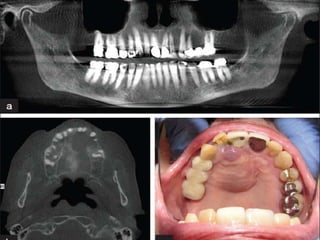

Central giant cell granuloma of the jaws is a benign

tumor which occurs most often in children and young

adults.



This tumor is made up of loose fibrous connective tissue

stroma with many interspersed proliferating fibroblasts,

aggregations of multinucleated giant cells, and foci of

hemorrhage.

.

Various surgical and nonsurgical treatments

havebeen advocated for this lesion.

Mainly treatment for CGCG is surgical.

One of the nonsurgical treatments proposed is

intralesional corticosteroid injection

Intralesional injection of triamcinolone acetonide has

been shown to induce partial and in some cases

complete resolution of central giant cell granuloma.

Equal parts of triamcinolone acetonide (10 mg )& lidocaine

(0.5%),3 ml of solution was injected into the lesion by multiple

penetrations with a needle of 0.5 mm diameter.

The mechanism of action of corticosteroids in the treatment of

central giant cell granuloma is unknown.

rationale for its use has been histologic resemblance of

CGCC to sarcoid. corticosteroids have been effective in the

treatment of sarcoid, it may have a similar therapeutic effect

on central giant cell granuloma.